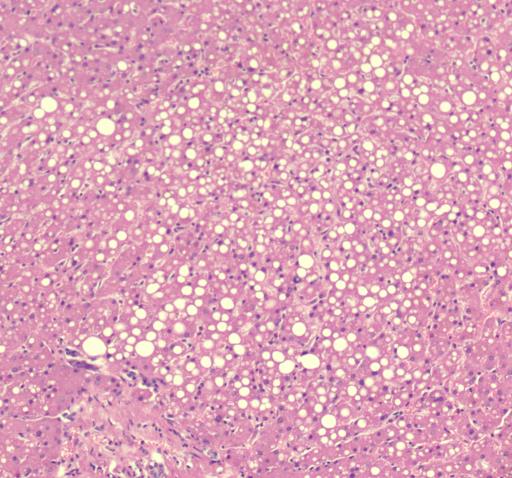

肝脏镜下情况 肾脏镜下情况